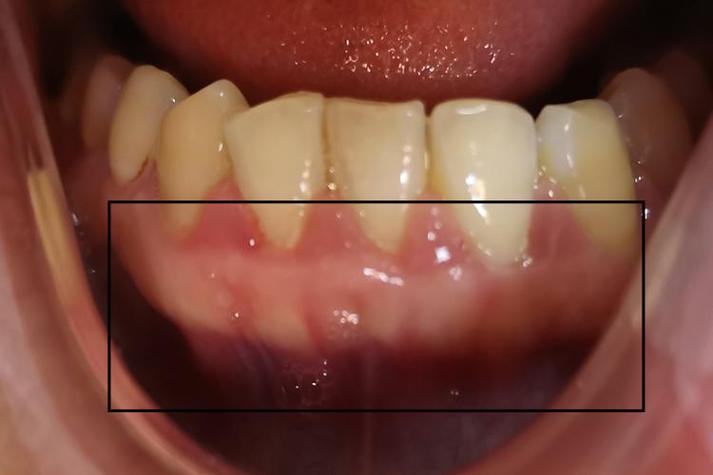

中度增生

- 临床表现:牙龈乳头和牙龈缘明显肿大,呈鲜红色或暗红色,质地松软,易出血,增生组织覆盖牙面1/3-1/2,可能形成“假性牙周袋”,食物嵌塞风险增加,部分患者有胀痛感。

- 图片特征:牙龈乳头呈球形膨出,与邻牙之间形成“V”形或“U”形凹陷,表面光滑或呈分叶状,探诊深度增加(图片中可见牙龈组织明显突出,覆盖部分牙面,牙龈乳头肿大如“小球”,颜色鲜红)。